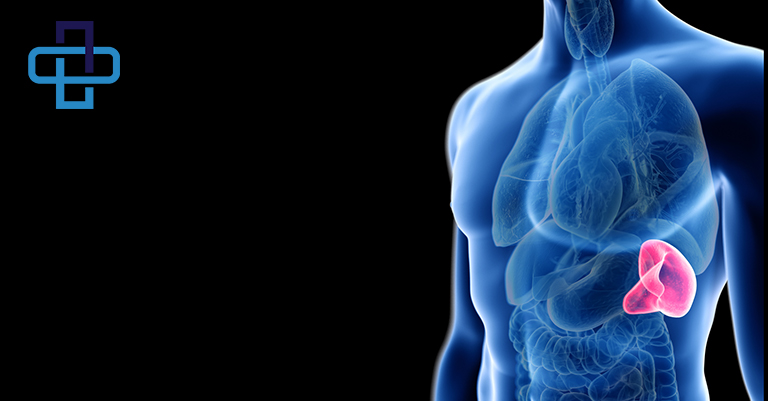

Τί είναι ο σπλήνας;

Ο σπλήνας αποτελεί ένα όργανο της περιτοναϊκής κοιλότητας που βρίσκεται στο αριστερό άνω μέρος της κοιλιακής χώρας. Είναι ένα από τα όργανα του λεμφικού συστήματος του ανθρώπινου οργανισμού. Το μέγεθος του μοιάζει με αυτό της ανθρώπινης γροθιάς. Λόγω της θέσης του κάτω από τις αριστερές πλευρές, δεν είναι φυσιολογικά ψηλαφητός και γίνεται αντιληπτός ψηλαφητικά όταν αυξάνει σε μέγεθος.